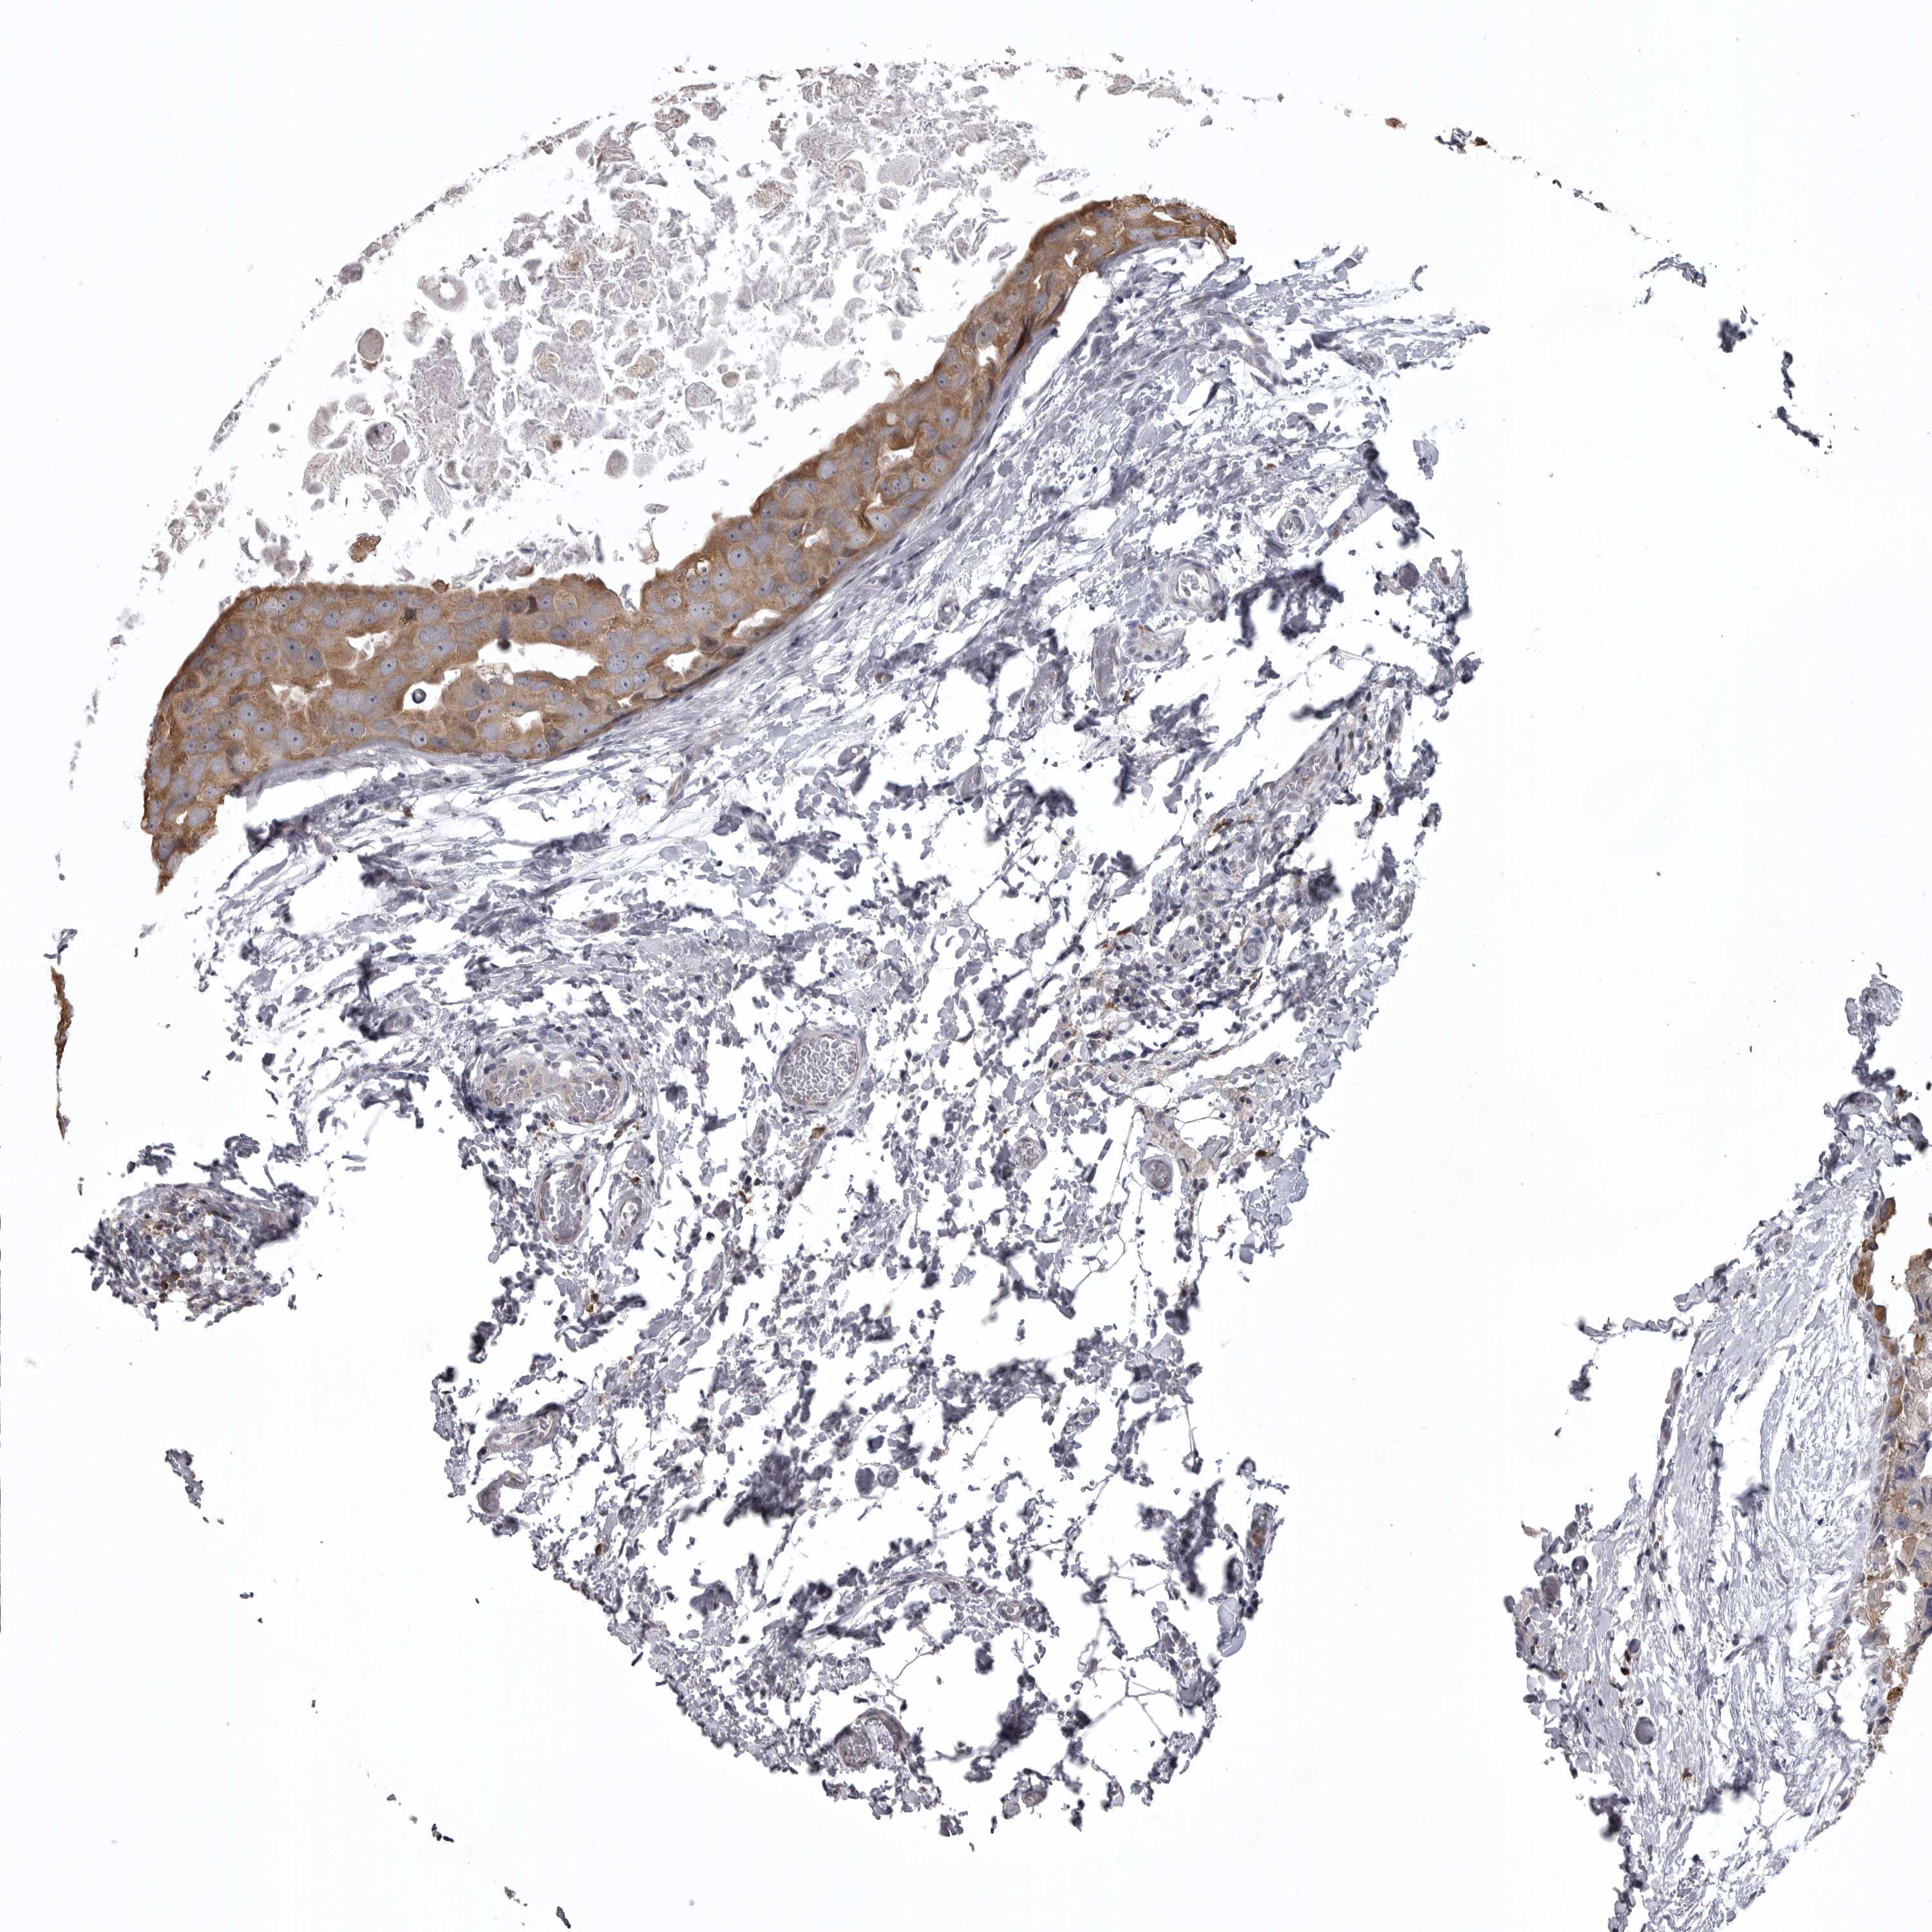

BRCA TCGA BRCA VALIDATION PROTEIN EXPRESSION

ANTIBODIES

AND

VALIDATION